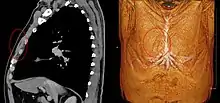

Sternalis muscle visible in an individual who also has an accessory abdominal pectoralis major, and an axillary arch of the latissimus dorsi. Musculus sternalis seen at axial CT and volume rendering.

Musculus sternalis seen at axial CT and volume rendering.